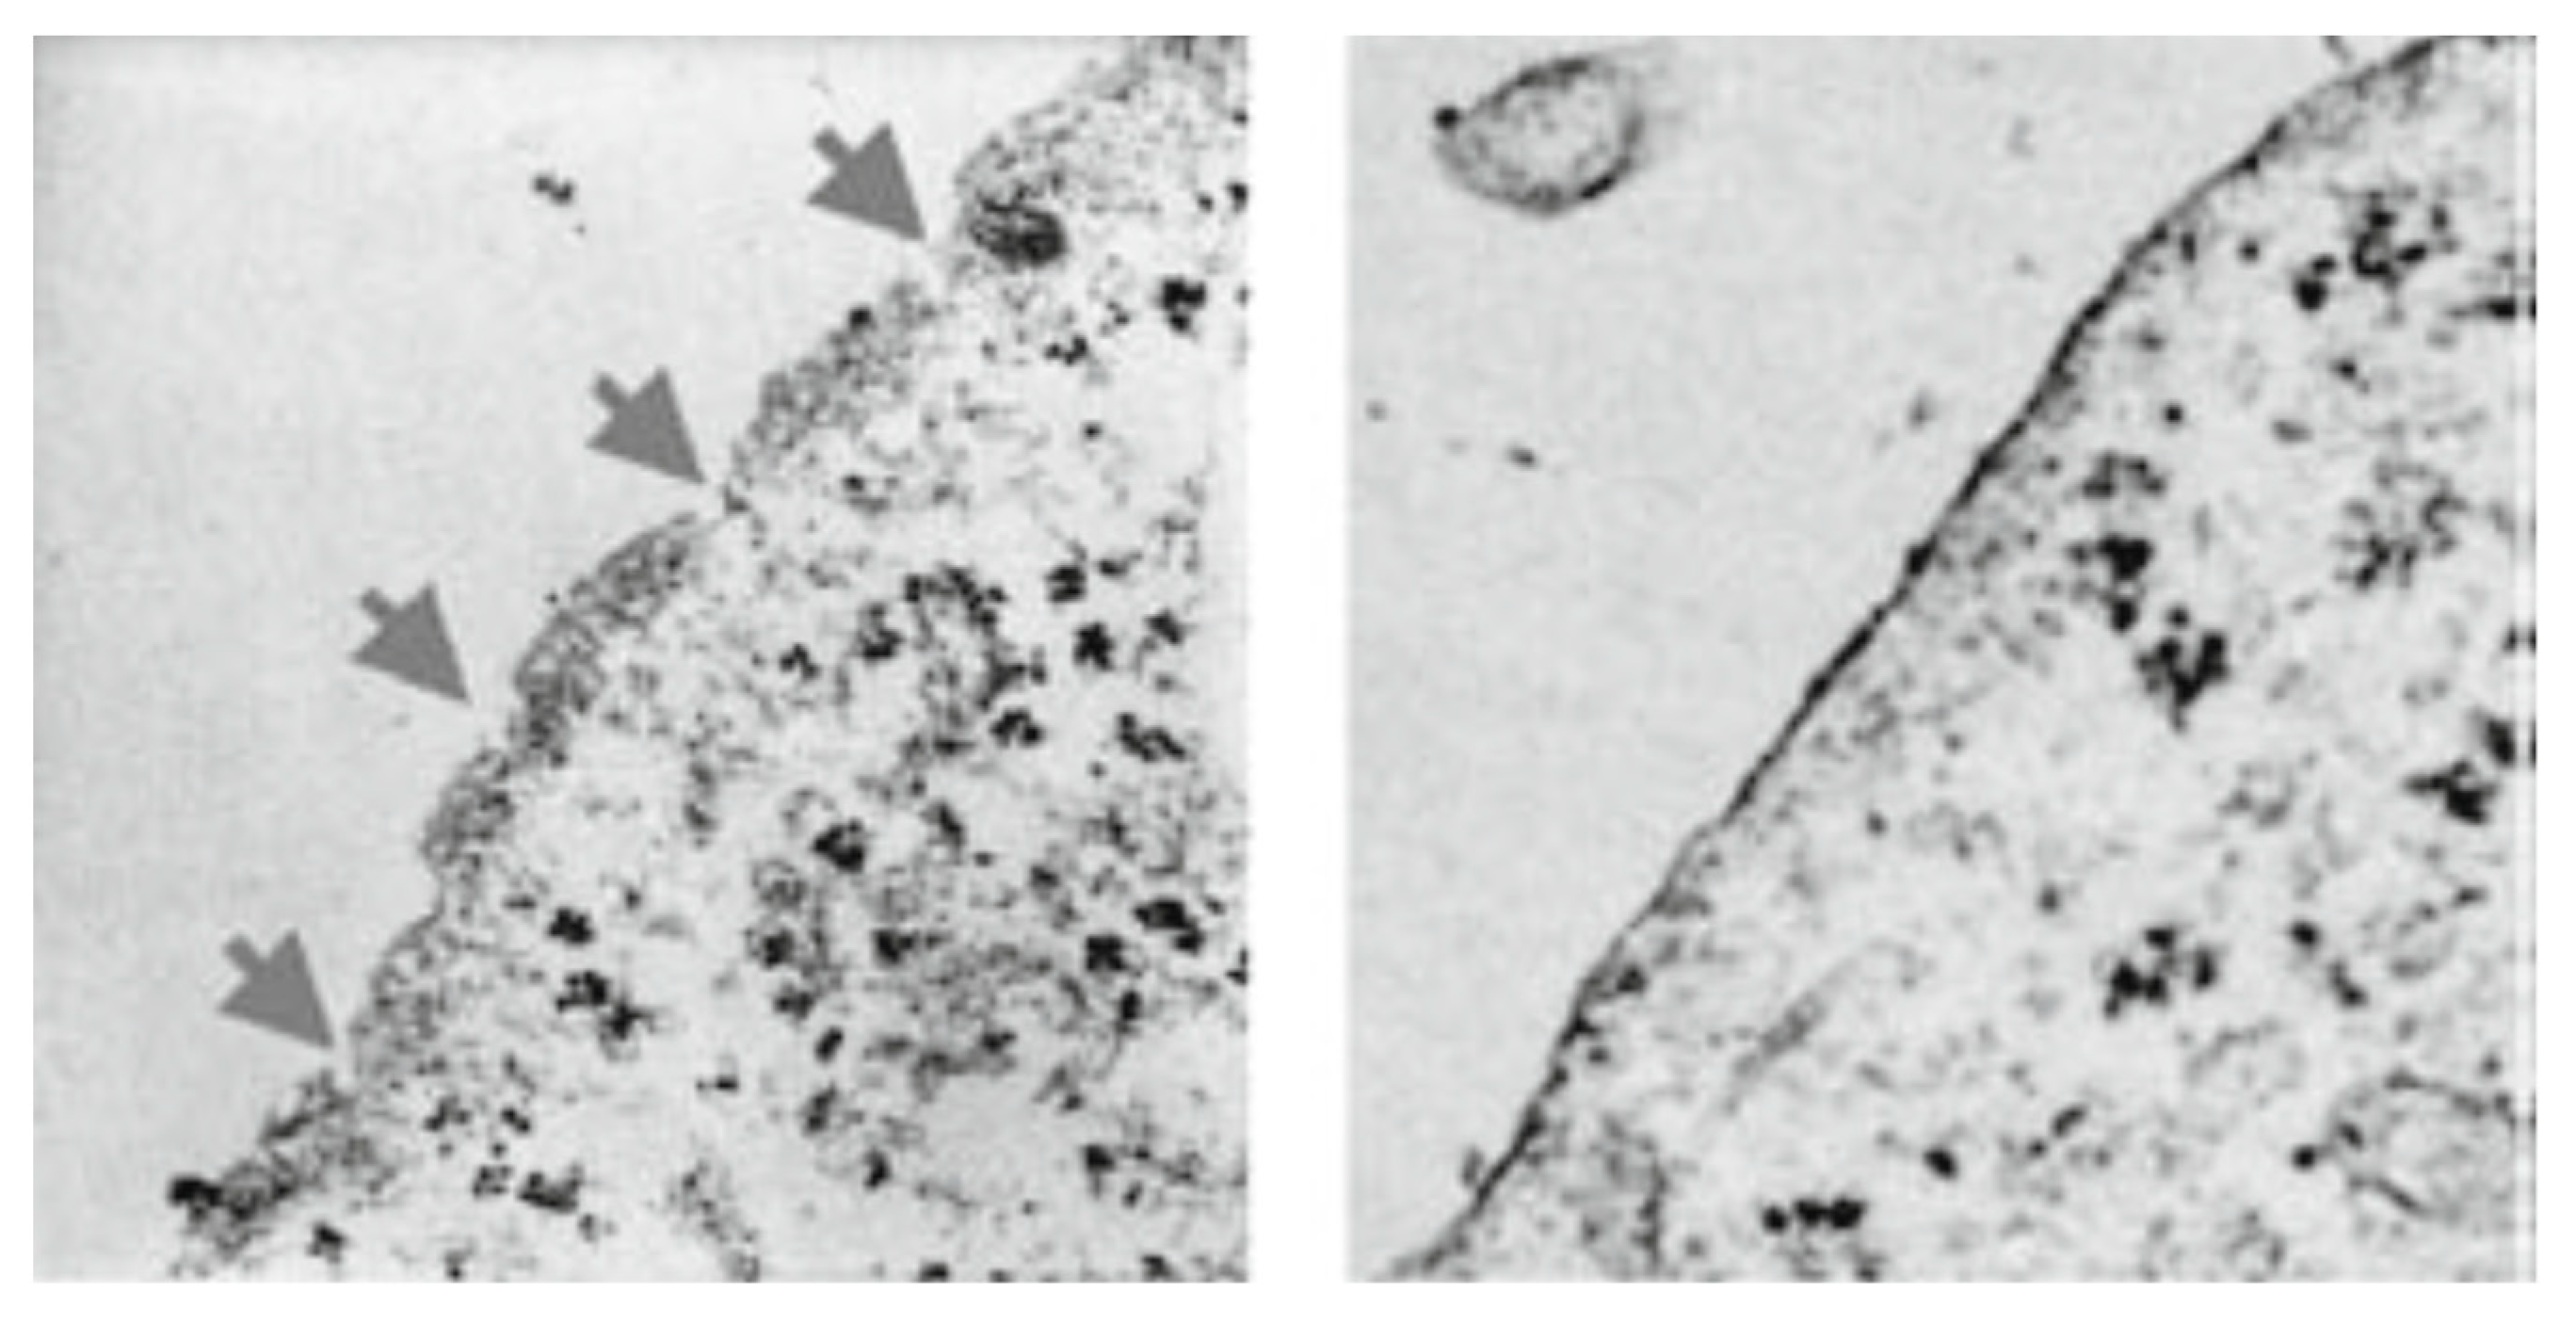

Since there is a rapid release of LDH indicative of membrane damage, we subjected tumor cells, i.e., breast cancer cells (MDA-MB-468) [13], pancreatic cancer cells (MIA-PaCa-2) [13], and melanoma cells (A2058) [13], to transmission electron microscopy after incubating them for 15 min with PNC-27 or PNC-28. As illustrated in Figure 3 for MIA-PaCa-2 cells incubated with PNC-28, pores were seen to form across the cell membranes of these cells, which were not seen in the case of untreated cells. As discussed below, no pore formation was observed in the electron microscopy when untransformed cells were incubated with either peptide. Time lapse photographs of cancer cells treated with PNC-27 show that this process is explosive, hence the term “poptosis”. The question arose as to how these PNC-27 and PNC-28 induced such pores.

Figure 3. Transmission electron microscopy of untreated MIA-PaCa-2 human pancreatic cancer cells (right frame) and MIA-PaCa-2 cells treated for 15 min with 100 μg/mL PNC-28 for 15 min in PBS (left frame). The arrows in the left frame point to discrete pores formed at regular intervals in the cancer cell membrane (reprinted from [19] by permission Annals of Surgical Oncology).